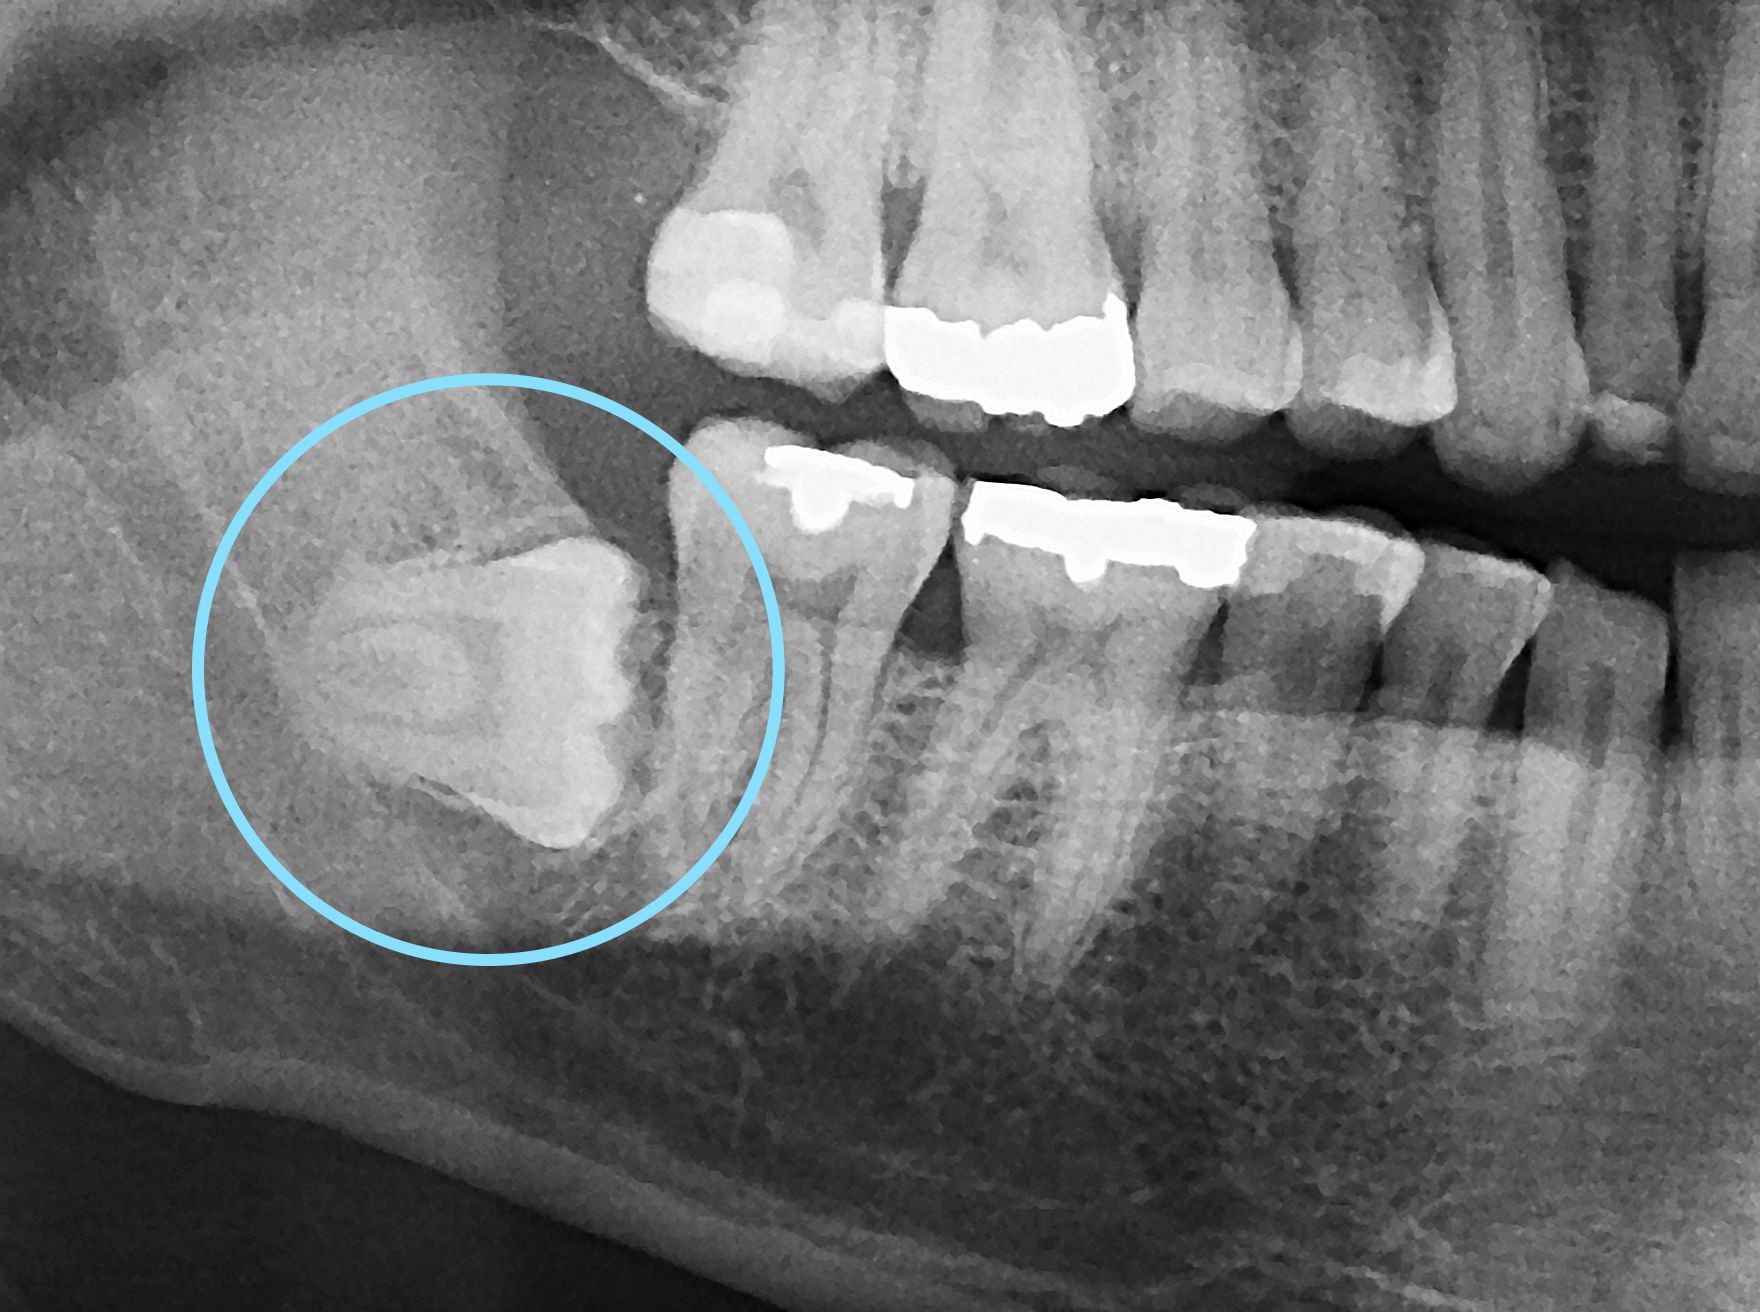

Les dents de sagesse EXTRACTION OU NON ? Chirurgie, douleurs, radiographie...Vous saurez tout